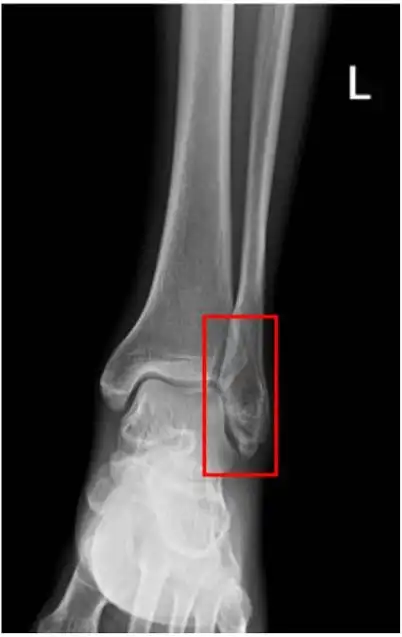

踝关节正位—x线

x光,足,正面视角,胫骨,腓骨